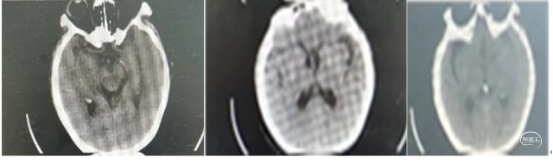

病史:患者入院2.5小时前休息时突发言语不利,难以与人交流,能理解他人言,右侧肢体无力,口角歪斜,行走、持物不能;双眼向左侧凝视。于11:30至我院急诊就诊,急查头颅CT未见颅内出血;CTA+CTP示左侧大脑中动脉M3闭塞,存在缺血半暗带。

术前CTA

手术过程

1、行右侧股动脉穿刺并置入8F动脉鞘成功。造影发现左侧大脑中动脉M3段以

远显影欠佳。正位不清晰,斜位清晰可见M3闭塞。

2、5F 125cm 中间导管抽吸:

泥鳅导丝引导8F导引导管至左侧颈内动脉C1远端平直处建立通路,微导丝引导微导管及5F 125cm 中间导管到达左侧大脑中动脉M3闭塞段近端。

近端使用60mL注射器手动抽吸两次,未见血栓取出。可能为导管未能接触血栓。

注意: 6F 125cm 中间导管到达大脑中动脉M1段; 5F 125cm中间导管到达大脑中动脉M2分叉以远。

3、换用3MAX 抽吸导管通路组合:

8F MPA+3MAX抽吸导管+微导丝,抽吸两次后栓子逃逸至远端分叉部。

5、 再次跟进3MAX抽吸一次,完全再通。

术后即刻复查XperCT未见出血。

术后第二天查看患者:神志清楚,应答切题,构音欠清晰。右上肢肌力2级,右下肢肌力3级。NIHSS评分8分。